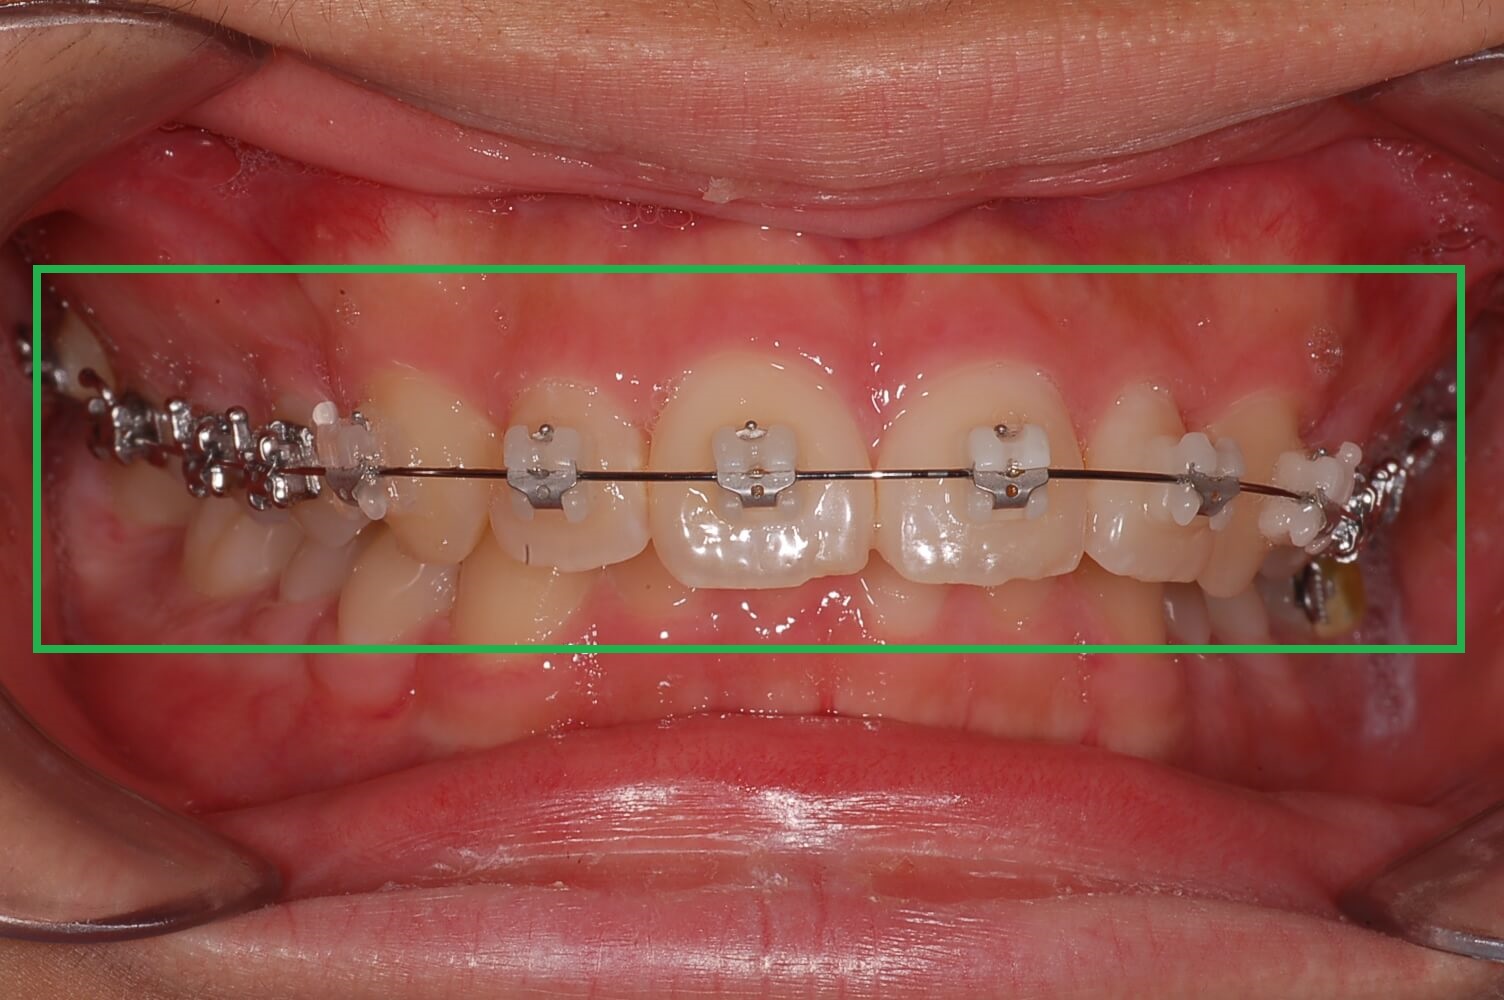

3. 가위교합 + 과개교합 교정실시 (전체브라켓 부착)

3개월간 가위교합 교정이 들어갔고 어느 정도 어금니가 제자리로 돌아왔습니다. 과개교합 교정을 위해 전체브라켓을 부착 하고 있는 사진입니다.

사진에 보면 철사가 S자 모양으로 휘어져 있습니다. 이 철사가 일자형으로 복원이 되면서 틀어진 치아배열을 정돈한다고 하는데 정확한 전문지식은 아니니 참고만 해주세요.

▼ 어금니 교정 후 전체 브라켓 부착

전체 교정 브라켓을 부착 후 2달 정도 지나고 나니 S자로 휘어진 철사가 어느 정도 일자로 복원되면서 앞니의 치아배열이 가지런하게 정리가 되어있습니다.